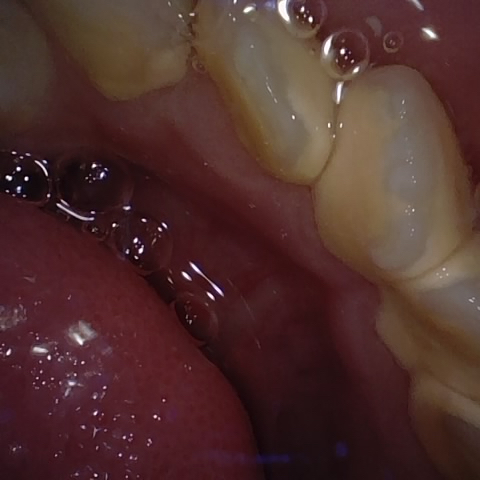

Annotated as "Good"

Original Image Rendering Image